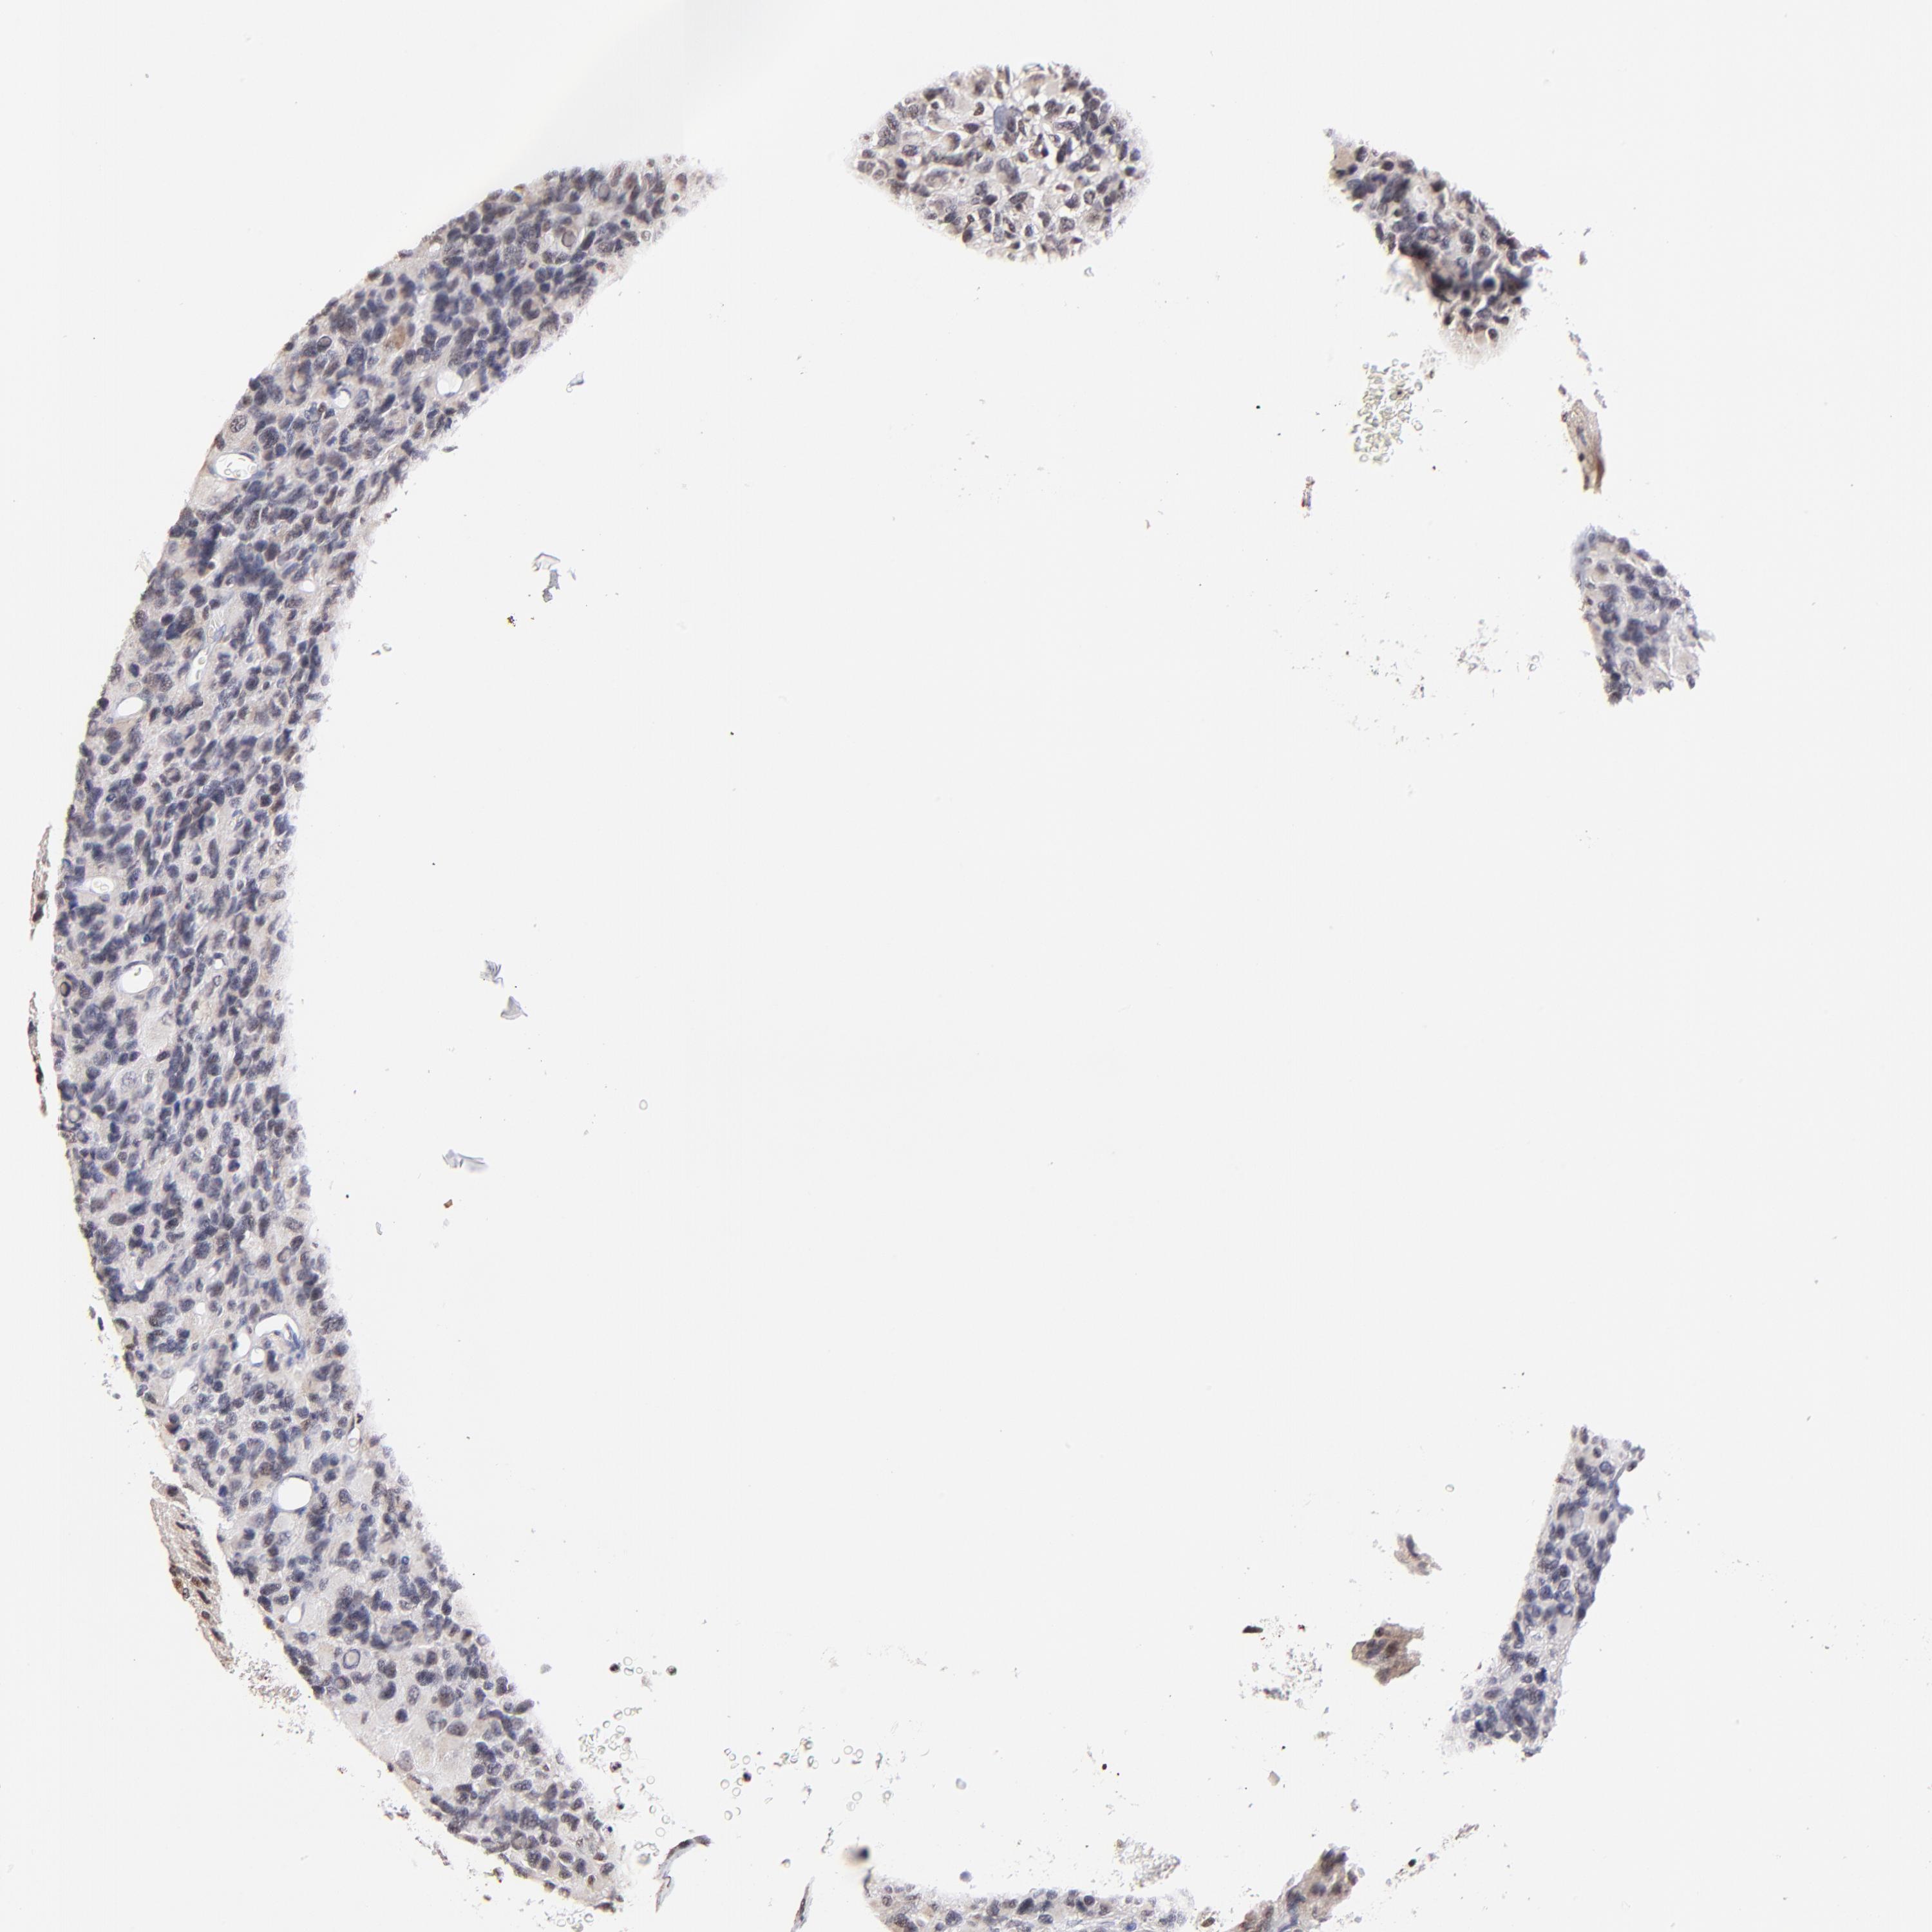

GLIOMA - Protein expressioni

A mouse-over function shows sample information and annotation data. Click on an image to view it in a full screen mode. Samples can be filtered based on level of antibody staining by selecting one or several of the following categories: high, medium, low and not detected. The assay and annotation is described here.

Note that samples used for immunohistochemistry by the Human Protein Atlas do not correspond to samples in the TCGA dataset.

Antibody stainingi

Antibody staining in the annotated cell types in the current human tissue is reported as not detected, low, medium, or high, based on conventional immunohistochemistry profiling in selected tissues. This score is based on the combination of the staining intensity and fraction of stained cells.

Each image is clickable and will lead to virtual microscopy that enables deeper exploration of all samples and also displays staining intensity scores, fraction scores and subcellular localization as well as patient and tissue information for each sample.

Antibody HPA003142

Staining

High

Medium

Low

Not detected

Intensity

Strong

Moderate

Weak

Negative

Quantity

>75%

75%-25%

<25%

None

Location

Nuclear

Cytoplasmic/membranous

Cytoplasmic/membranous,nuclear

Glioma, malignant, High grade

Glioma, malignant, Low grade